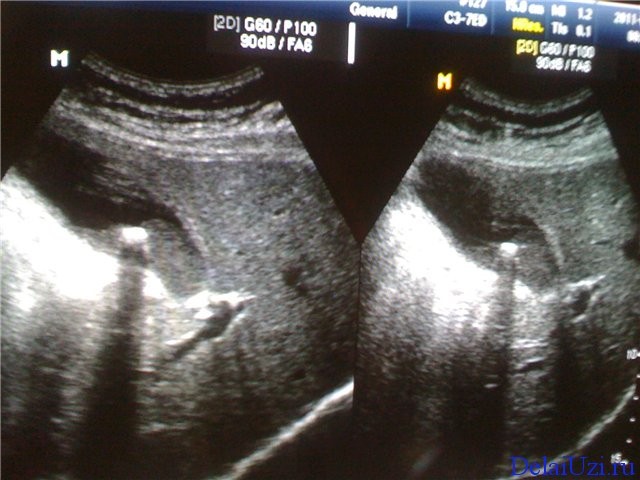

- При исследовании четко визуализируется анатомическое строение органа: головка, перешеек, крючковидный отросток и хвост. У каждого отдела железы есть своя норма показателей. Небольшие отклонения допустимы лишь при хороших биохимических анализах крови. Головка, толщина норма – до 32 мм, тело примерно до 21 мм, а норма хвоста до 35 мм.

Измененные размеры при УЗИ поджелудочной железы не столь важная величина. Гораздо важнее совокупность нескольких показателей. Если контуры железы четкие и ровные, как того требует норма, значит функция и состояние этого органа будут удовлетворительными.

Особую важность представляет состояние протока железы (Вирсунгов проток). Если есть какие-либо изменения, то возникают подозрения на опухоль головки железы или панкреатит.

При прогрессировании панкреатита до некротической стадии на поверхности железы могут появляться псевдокисты. Если расшифровка результатов исследования осуществляется квалифицированным специалистом, он сможет выявить распад тканей органа. В запущенных случаях могут наблюдаться очаги с абсцессами на стенках брюшной полости и сальниковой сумки.